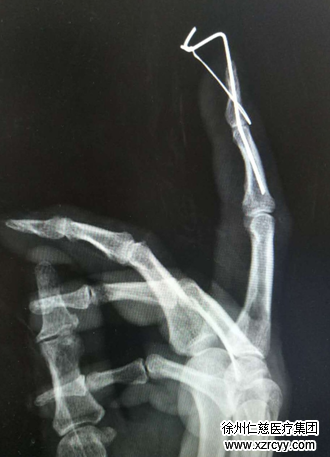

受伤后,韩阿姨在当地医院简单包扎后,和家人立即赶往betway在线登陆。经手外科四病区的厉程医生诊断,韩阿姨右中指远节锤状畸形,远指间关节背侧可见一“L”型撕脱伤口,深达骨质,创缘不齐,挫伤重,伤口内可见伸肌腱自止点断裂,远指间关节脱位。厉程医生手术小组随即为韩阿姨实施了“右中指清创+关节脱位复位内固定+伸肌腱止点重建术”。

“这对我们专业的手外科医生来说,其实是个小手术,但考虑到让患者术后能得到更好的恢复,我们采取了一个新技术。”厉程医生介绍,他们在术中彻底清除患者右中指伤口污染失活组织,修剪创缘后,将1根1.0mm克氏针自指端纵行打入固定,然后用1根0.4mm钢丝贯穿伸肌腱,将伸肌腱固定于远节指骨背侧基底部止点处,线尾自远节指腹穿出固定于克氏针处。

“简单点说,这位患者手指的肌腱断了,筋从骨头上被拽下来了,我们用钢丝牵拉的方法,把筋往骨头上牵拉住,以便筋能慢慢和骨头长在一起。”厉程医生讲解到,按照以往的办法,医生会在伤口处固定一个纽扣,在纽扣下面垫上纱布,把钢丝牵拉到纽扣上,起到牵拉加压的作用,可这种操作容易挤压到指腹的皮肤,影响患者更好的恢复。“这一次我们把克氏针折弯了,用克氏针的力量牵拉钢丝,既能给肌腱压力,又不会压到皮肤,让患者康复起来无任何后顾之忧。”